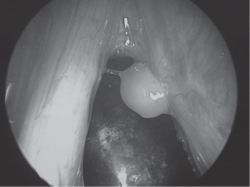

8. What is the most likely diagnosis for the lesion seen in the photo below? (See Fig. 18-5.):

FIG. 18-5.

A. Laryngeal granuloma

B. Polypoid laryngitis

C. Vocal cord cyst

D. Leukoplakia of the vocal cord

Answer: A

Laryngeal granulomas typically occur in the posterior larynx on the arytenoid mucosa.

Edema in the superficial lamina propria of the vocal cord is known as polypoid corditis, polypoid laryngitis, polypoid degeneration of the vocal cord, or Reinke’s edema.

Vocal cord cysts may occur under the laryngeal mucosa, particularly in regions containing mucous-secreting glands, such as the supraglottic larynx.

Leukoplakia of the vocal fold represents a white patch (which cannot be wiped off) on the mucosal surface, usually on the superior surface of the true vocal cord. (See Schwartz 9th ed., p 484.)